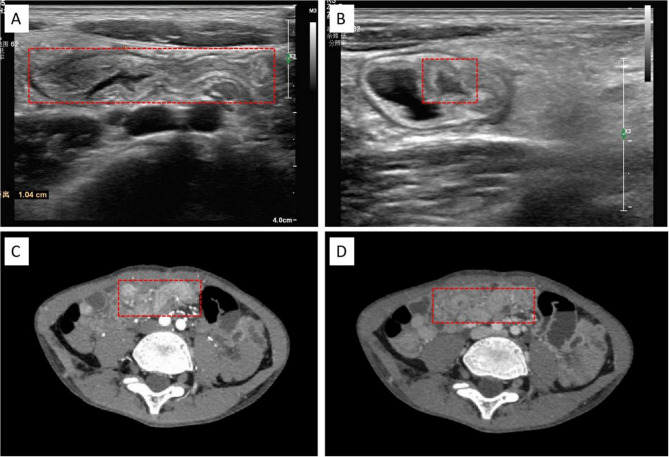

Case presentation: An 8-year-old male patient was admitted with "abdominal pain for 20 days." After admission, abdominal ultrasound and computed tomography (CT) scans suggested a small bowel lesion, possibly Meckel's diverticulum. Following comprehensive preoperative evaluations, we performed single-site laparoscopic exploration via the umbilicus. Intraoperatively, long segment (60 cm) small bowel duplication was identified, and laparoscopic-assisted resection of the duplicated bowel was performed, with good postoperative recovery.